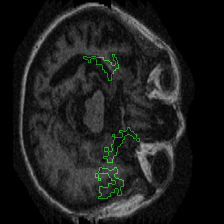

Figure 1 presents attribution maps generated using PWIG for a selection of MRI scans across all four diagnostic categories. The highlighted regions (in green) correspond to the areas that contributed most significantly to the model’s decision. Notably, we observe consistent emphasis on anatomical structures that align with clinical markers of dementia, including cortical and subcortical regions. For instance, in the moderate and mild dementia examples, the model focuses on regions exhibiting visible atrophy or abnormal morphology. In contrast, attribution maps for non-demented subjects appear more diffuse and less concentrated, reflecting the model’s detection of normal anatomical patterns.

The results in Figure 1 demonstrate that PWIG can effectively produce interpretable and clinically meaningful explanations for model predictions in medical imaging tasks.

Figure 1: PWIG attribution maps across dementia categories using the OASIS-1 dataset. Green overlays indicate regions with the highest attribution scores.